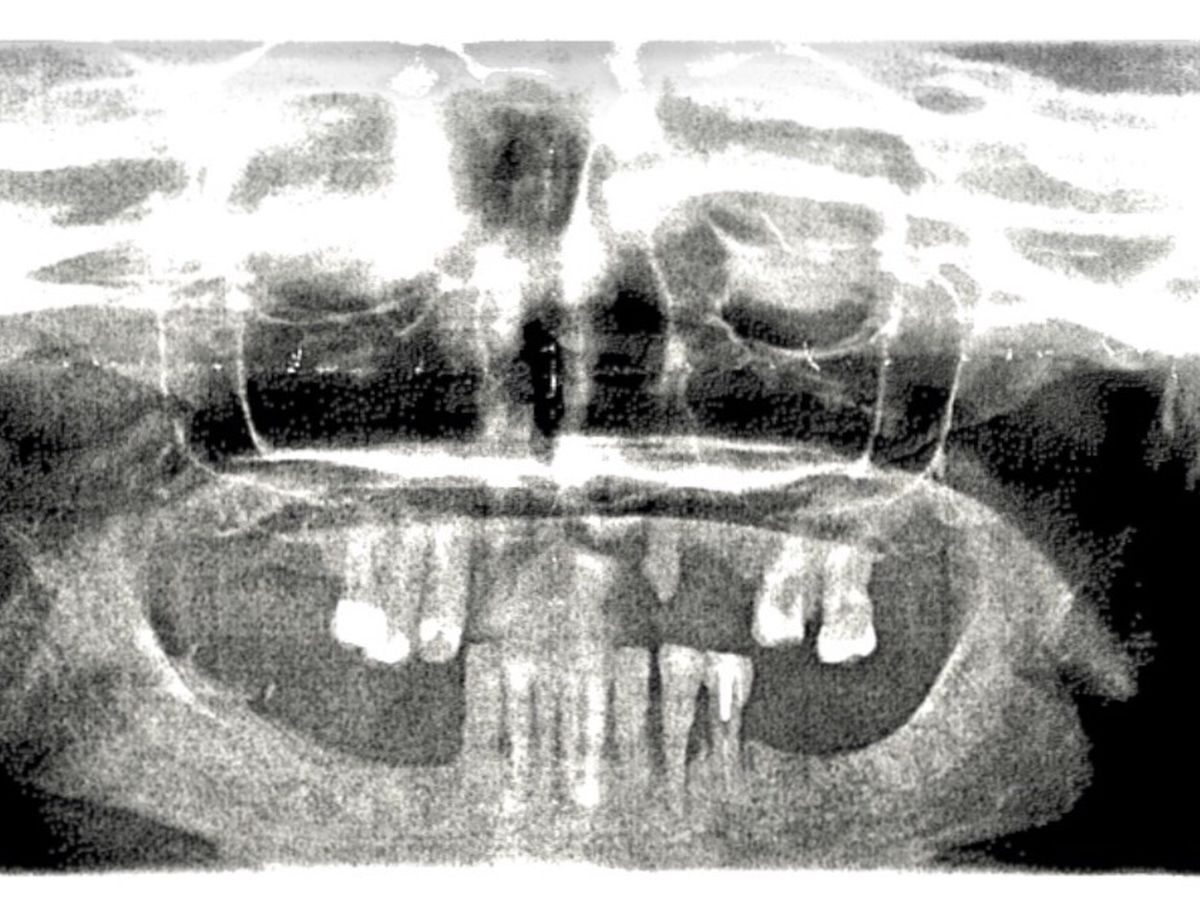

Hello, my name is Frank, and I am helping KC, who is very very dear to me, to smile once again. I have started this campaign on Go Fund Me in order to raise the appropriate funds necessary for KC to receive her much-needed reconstructive dental surgery. This reconstructive surgery isn't for cosmetic purposes. She needs bone graphing, a major sinus lift, and extractions. This entire situation has been extremely traumatic on KC, resulting in severe depression and seclusion. This is not only about a smile it's about her optimal health and well-being. Your contributions to this campaign will be truly life changing for KC, and it would be greatly appreciated. Thank you so much